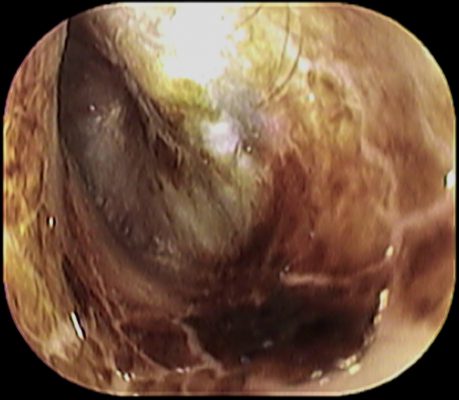

耳の乳児湿疹のケア方法 ジュクジュクしている 耳の後ろがただれている Kosodate Life 子育てライフ

生後66日 耳の裏がジュクジュクに 乳児湿疹とステロイド軟膏の効果 ママディア